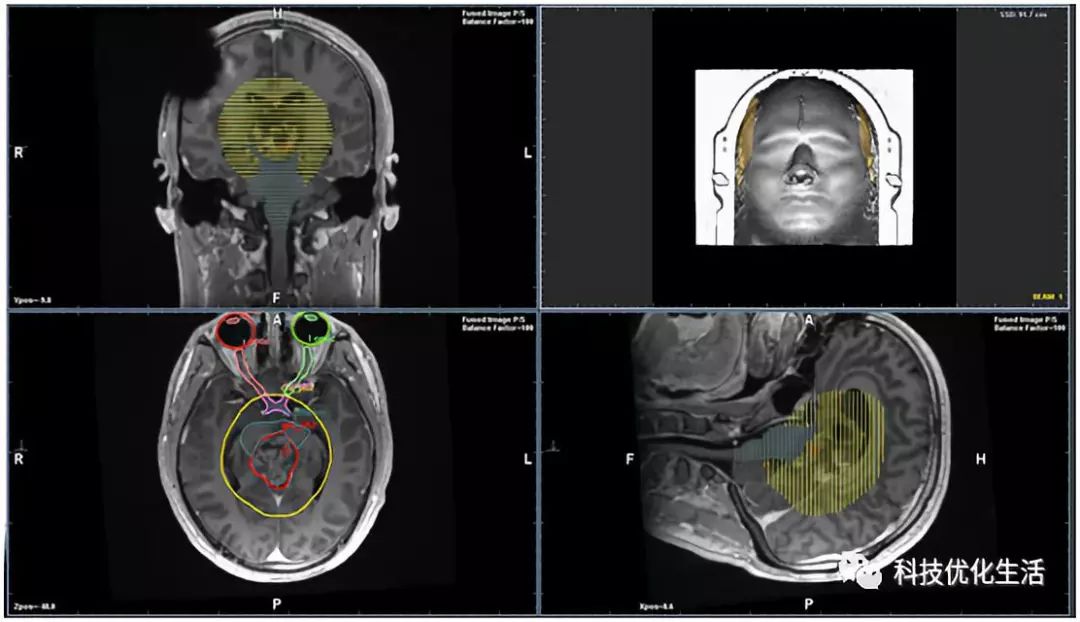

来自英国剑桥大学的神经肿瘤学家Raj Jena在过去的六个月中,使用名为InnerEye的AI系统标记前列腺癌患者的扫描结果。扫描完成后,图像被匿名化并加密发送到InnerEye程序,即可描述相关结果情况,并创建3D模型。该软件通过大量的机器学习,目前已经学会了如何标记器官和肿瘤,大大为前列腺癌治疗节省了时间(男人的福音啊)。